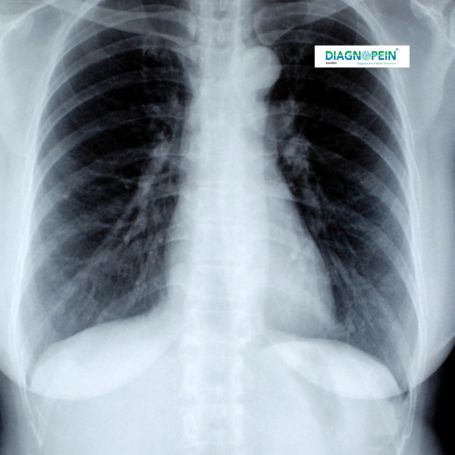

CT Chest Abdomen Contrast is an advanced diagnostic CT scan used to examine the chest, lungs, heart, liver, kidneys, pancreas, spleen, and abdominal organs with precision. This CT scan with contrast in Nashik uses a safe contrast dye injection to enhance visibility of blood vessels and tissues, making it easier to detect even minor abnormalities.

At Diagnopein Nashik, our high-quality Multislice CT Chest Abdomen Contrast Scan offers cross-sectional imaging with optimal clarity. The test is recommended for patients with symptoms like chronic cough, chest pain, liver disorders, abdominal swelling, or suspected infection or tumor.

The CT Chest Abdomen Contrast test is vital for diagnosing diseases where chest and abdominal symptoms overlap. It provides a complete internal overview in one scan, minimizing the need for multiple tests. In medical imaging Nashik, this scan helps doctors detect infections, tumors, internal injuries, and inflammation accurately.

Using a contrast-enhanced CT scan, the radiologist can clearly identify structures like airways, lung tissue, and abdominal organs. It assists in detecting conditions such as pneumonia, tuberculosis, lung cancer, aortic aneurysms, liver fibrosis, gallstones, ulcers, or renal stones.